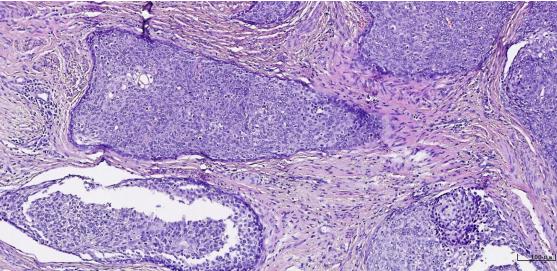

病变组织制成厚约数微米的切片,通常用苏木精·伊红染色(HE染色),或其他方法染色后,用光学显微镜观察其微细病变。

到目前为止,传统的HE染色组织学观察方法仍然是病理学诊断和研究最基本的方法,还没有其他方法能够取代。